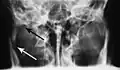

- Towne's view of a bilateral condyle fracture. White arrow is a fracture on the neck of the condyle. Black arrow shows the condyle pulled to the medial. The same injury can be seen on the opposite side